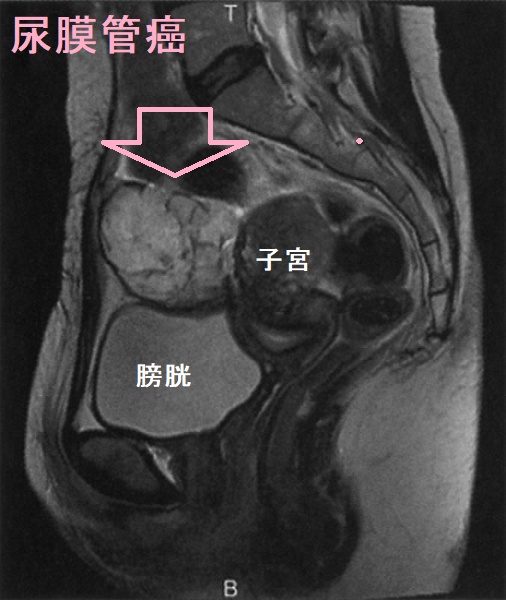

尿膜管癌 腹部MRI T2強調矢状断像

尿膜管癌 腹部MRI T2強調矢状断像;腫瘤と膀胱筋層は接しているが、明瞭に区別できる。